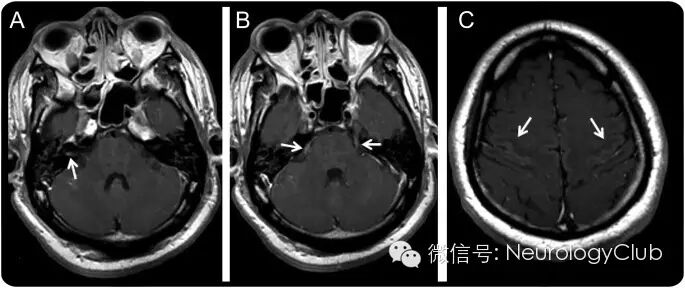

巢式PCR检查在脑脊液和唾液中均发现了狂犬病毒。起初的增强MRI正常。第8天复查神经影像学提示颅神经强化,双侧尾状核轻度信号轻度增高。

(A:T1增强示内听道第7、8颅神经强化;B:双侧第5对颅神经强化;左侧第3和第9颅神经强化[未放图];C:中央前后回附近皮层轻度强化;左侧尾状核头部轻度高信号[未放图]。)